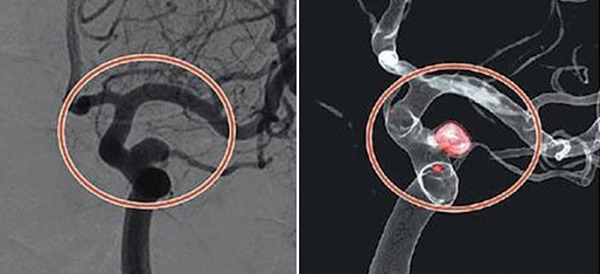

코일색전술은 뇌를 열지 않고 혈관 내에서 동맥류를 치료하는 방법으로, 대퇴동맥을 통해 삽입한 카테터를 이용하여 동맥류 내부에 백금 코일을 채워 혈류를 차단하는 시술입니다. 이를 통해 동맥류의 파열을 방지할 수 있습니다.

코일색전술은 모든 뇌동맥류에 적용할 수 있는 것은 아니며, 동맥류의 위치, 크기, 모양, 환자의 전반적인 건강 상태 등을 종합적으로 고려해야 합니다. 또한, 시술 후 정기적인 추적 검사가 필요합니다. 코일이 제대로 자리 잡고 있는지, 재발 가능성이 없는지를 확인하기 위해 CT 또는 MRI를 통한 검사가 주기적으로 시행됩니다.